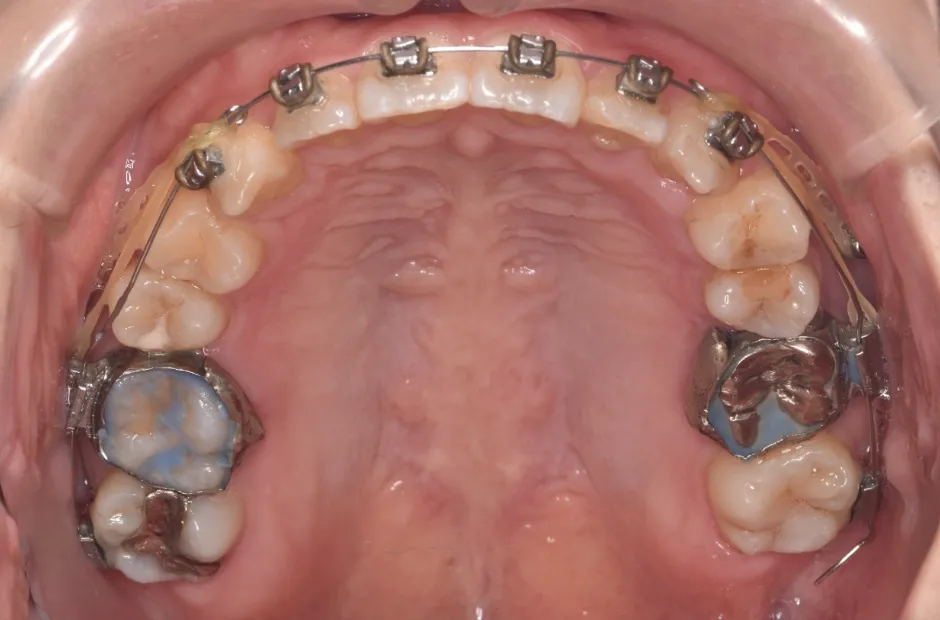

治療中